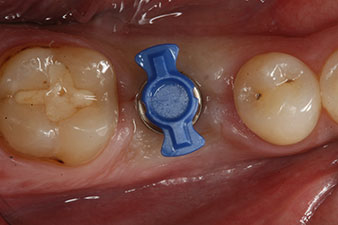

Въртящият момент, използван за машинно-задвижвано поставяне, е 43 Ncm. Освен това, след завинтване на измервателния щифт (SmartPeg), специално пригоден за импланта, стойността на ISQ се измерва със сондата на W&H Osstell ISQ модула.

Този модул е допълнителна екстра към Implantmed на W&H и е закачен към имплантологичния мотор (виж фиг. 11). Липсата на ISQ стойност непосредствено след поставянето е 64 оровестибуларно и 68 мезиодистално (максимална стойност = 100).

Тези стойности могат да показват отворено лечение или дори имедиатно възстановяване. Поради недостатъчния обем на кресталната кост при импланта, областта е подсилена с костните частици, събрани по време на препарацията на имплантното ложе и зашити, за да се изолира слюнката.